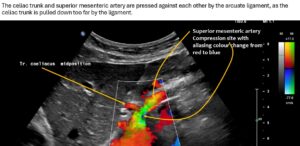

The systolic flow velocity in the abdominal aorta is only 80 cm/s. This indicates the compliance of the aortic vessel wall. However, in the celiac trunk, there are significantly increased flow velocities that vary with breathing, namely 161 cm/s in the middle respiratory position, 287 cm/s during inspiration, and 210 cm/s during expiration. This indicates ligamentum arcuatum syndrome, whose typical symptoms are vegetative symptoms such as nausea, circulatory dysregulation, disturbed peristalsis, sudden skin redness, and loss of appetite, as well as, of course, severe postprandial epigastric abdominal pain—the patient’s main symptom.

The arcuate ligament pushes the celiac trunk so far caudally that it leads to secondary compression of the superior mesenteric artery.

As a result of the compression, turbulent, highly accelerated flows are found in the vessel outlet, with 240 cm/s in the middle respiratory position, 226 cm/s during inspiration, and 196 cm/s during expiration.